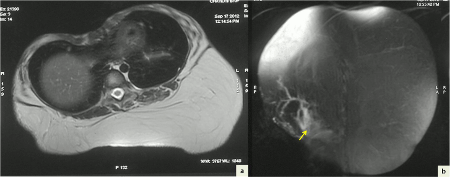

A six-year-old girl presented with a gradually enlarging painless lump in the right upper back since birth. Local examination revealed a 20 cm x 20 cm soft non-tender lump in the subcutaneous tissues of the back. MRI scans showed a large lobulated mass lesion with predominantly fat intensity on T1-weighted and T2-weighted images. Multiple septae were seen within the lesion. The right inferolateral aspect of the mass showed a small soft tissue component with minimal enhancement on gadolinium contrast (Fig. 1). Fine needle aspiration (FNA) smears showed adipose tissue fragments composed of mature adipocytes as well as lipoblasts with multivacuolated cytoplasm, central indented normochromatic nucleus without nucleoli (Fig. 2a, 2b). A cytologic impression of lipoblastoma was rendered. The child underwent in-toto resection of the tumor. Cut-section of the mass showed a lobulated appearance with yellow and focal grey-white areas. Multiple sections showed a lobulated adipocytic tumor composed predominantly of mature adipocytes separated into lobules by fibrous septae. The septae showed stellate cells and occasional multivacuolated lipoblasts with small central nucleus. No nuclear atypia, mitosis or necrosis was seen (Fig. 2c). Histopathology was consistent with lipoblastoma. The child is doing well one year after surgery.

Figure 1: Axial T2-weighted (a) and coronal fat-saturated (STIR) images (b) showing a large lobulated predominantly fat intensity lesion with multiple septae within the subcutaneous tissue of back. A soft tissue component is seen along its right inferolateral aspect (arrow in b). |